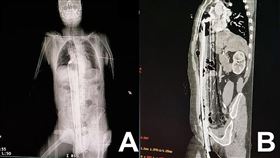

91公分鋼條從下體插入頂到肺 他奇蹟存活

巴西一個醫學團隊在最新一期《國際外科手術病例報告期刊...

2024/05/07 07:24